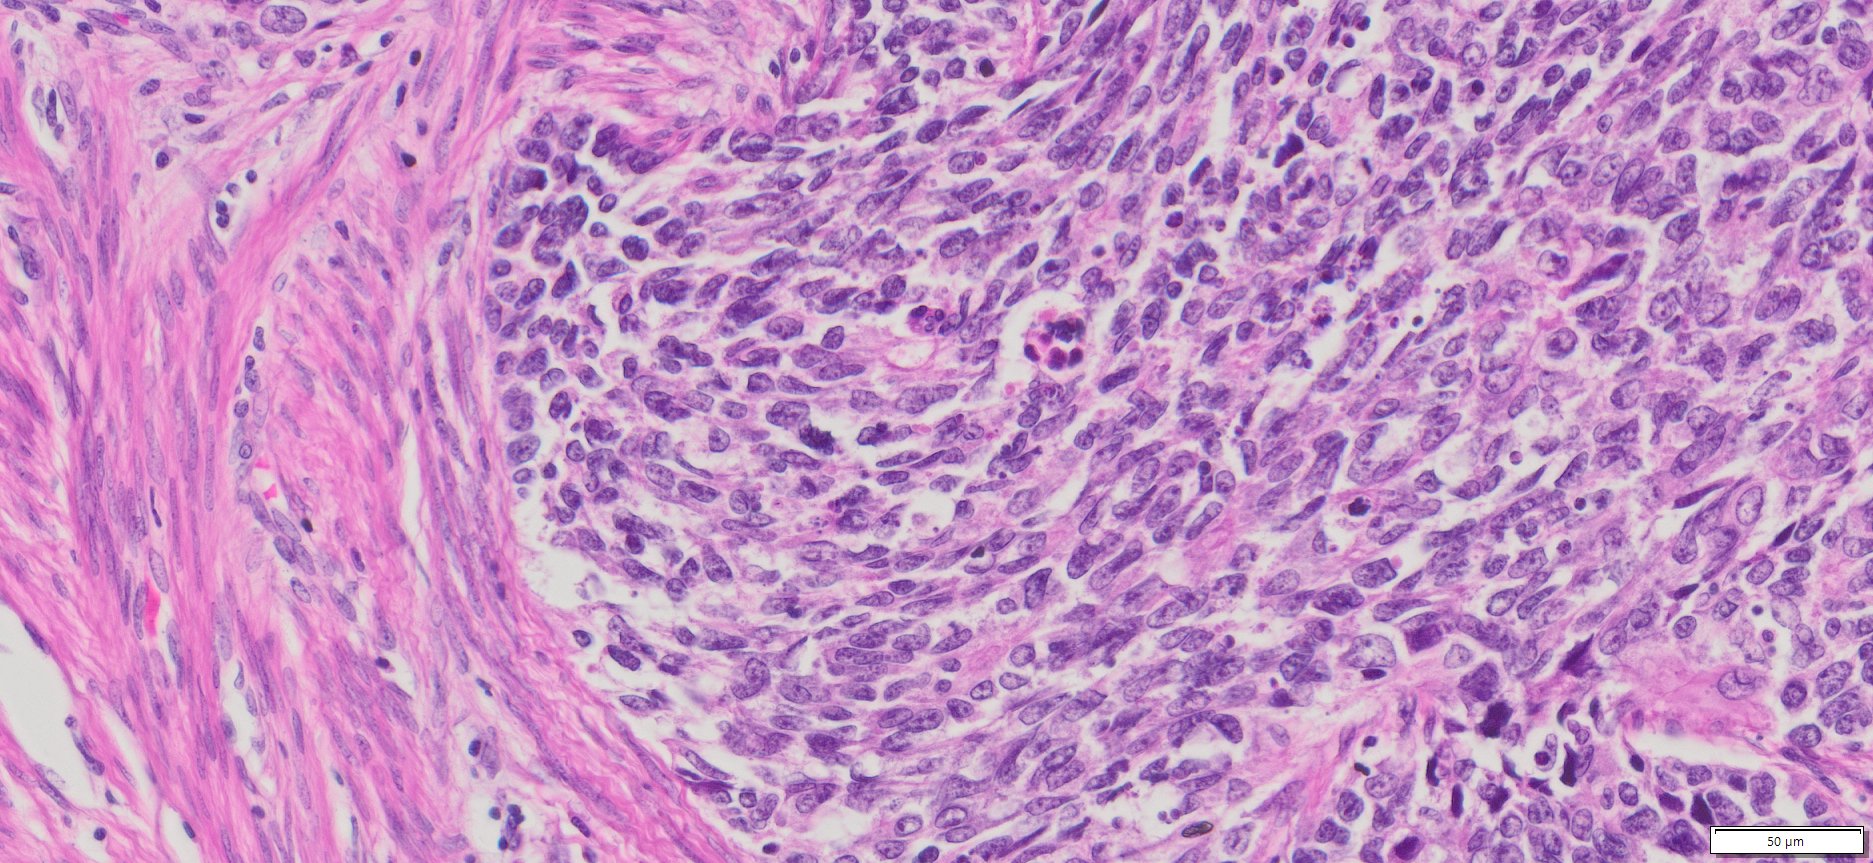

Description

| Organ& Tissue | Pathology Diagnosis | Gender/Age | % Tumor Area | Grade | TMN Stage | Biomarkers |

| Endometrial | Endometrial carcinosarcoma (malignant mixed Müllerian tumor) | Female/52 | 40% | NA | pT3apN1Mx | MLH1-2,MLH6 and PMS2: Intact nuclear expression |

More Images of H&E Stain and IHC